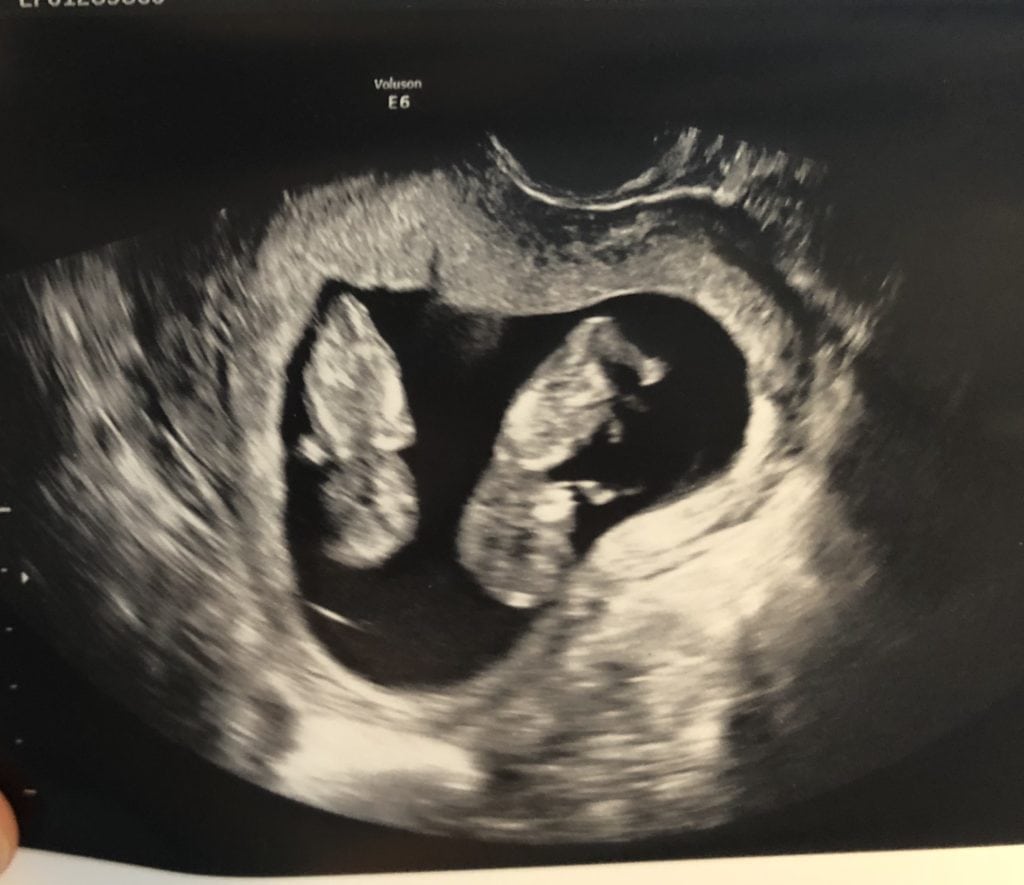

11 Weeks Pregnant Ultrasound Capturing the Wonder of Your Growing Bab What Is Baby In 11 Weeks How big is a baby at 11 weeks pregnant? Your baby, or foetus, is now around 41mm long from head to bottom, which is about the size of a fig. Your little one may measure more than 1 1/2 inches long. at 11 weeks pregnant, you’re in your third month of pregnancy, even though you may have no symptoms. What Is Baby In 11 Weeks.

11 Weeks Pregnant Ultrasound What Is Baby In 11 Weeks Let窶冱 take a look at what窶冱 happening in your. At 11 weeks, the baby is about the size of a brussels sprout. Your little one may measure more than 1 1/2 inches long. How big is a baby at 11 weeks pregnant? Learn more about what to expect with babycenter. Your baby, or foetus, is now around 41mm long from. What Is Baby In 11 Weeks.